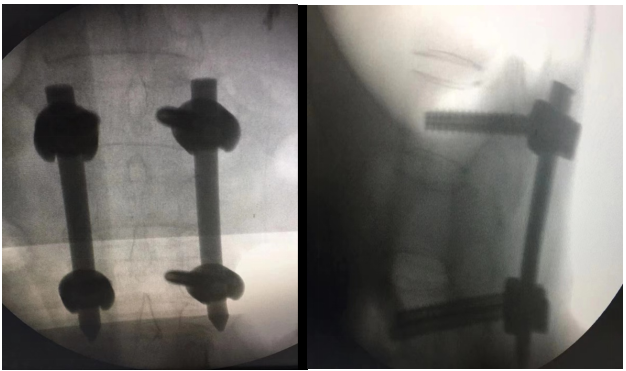

近日,我院骨与关节康复科成功开展经皮椎弓根内固定术治疗腰椎压缩性骨折。

据了解,患者因摔伤致胸腰背部疼痛入住我院,术前影像学检查提示腰椎(L1)椎体压缩性骨折,完善术前准备后给予经皮椎弓根内固定术治疗,术后患者恢复良好,术后早期可下床活动、康复锻炼。

经皮脊柱椎弓根钉内固定术

经皮脊柱椎弓根钉内固定术,相比传统开放手术,微创优势明显,椎旁肌肉损伤小,术后恢复快,已是目前治疗非骨质疏松性胸腰椎骨折常规治疗方式。